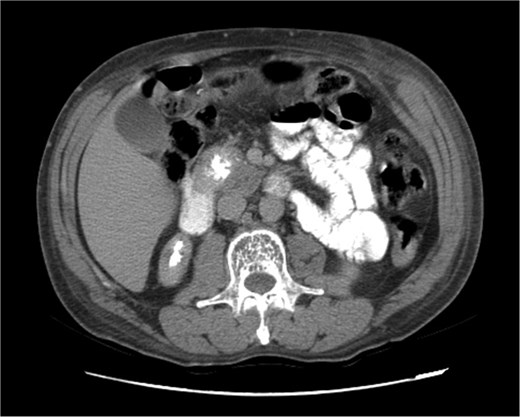

Upon admission in January 2025, the patient presented with altered mental status, dehydration, and hypoglycemia. The recurrence of hypoglycemic episodes was confirmed by laboratory studies and imaging, which identified a well-defined 3 cm mass in the pancreatic head on triphasic computed tomography (Figs 1–3). Given the diagnosis of recurrent malignant insulinoma and the possibility of resection, a surgical approach was chosen.

Triphasic computed tomography of the pancreas, portal phase, showing a tumor in the head of the pancreas.